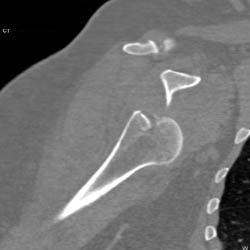

Diagnosis

Lipoma Left Thigh Presents as Mass